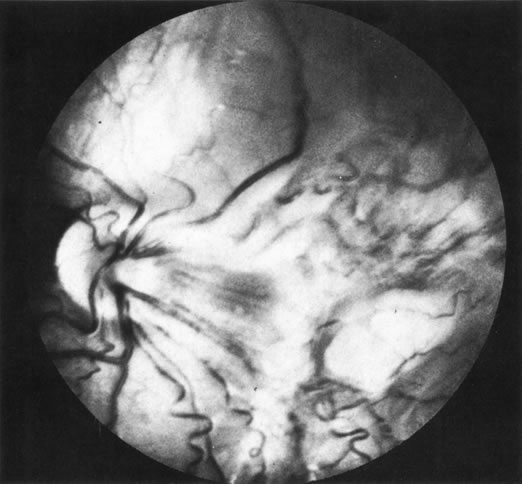

Necrotic melanomas account for approximately 5% of uveal melanomas; in the majority of cases, there is intraocular inflammation accompanying the cataract.7–9Figures 1 and 2 demonstrate a typical case. The patient had a long history of unilateral decreased vision. The eye had become painful 1 month before admission, and he was referred for evaluation of uveitis. Clinically, there was a dense, unilateral cataract with significant intraocular inflammation, which was manifested as a ciliary flush with 2+ cells and flare. Media opacity obscured all fundus detail. An immersion B-scan demonstrated a large intraocular tumor that was most consistent with a uveal melanoma. The eye was removed, and the diagnosis was confirmed histologically.10